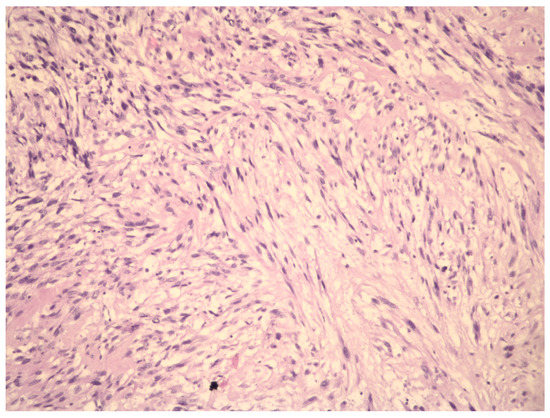

Molecular Insights in Uterine Leiomyosarcoma: A Systematic Review

3.2. Molecular Basis of Differentiation Uterine Leiomyosarcoma vs. Uterine Leiomyoma